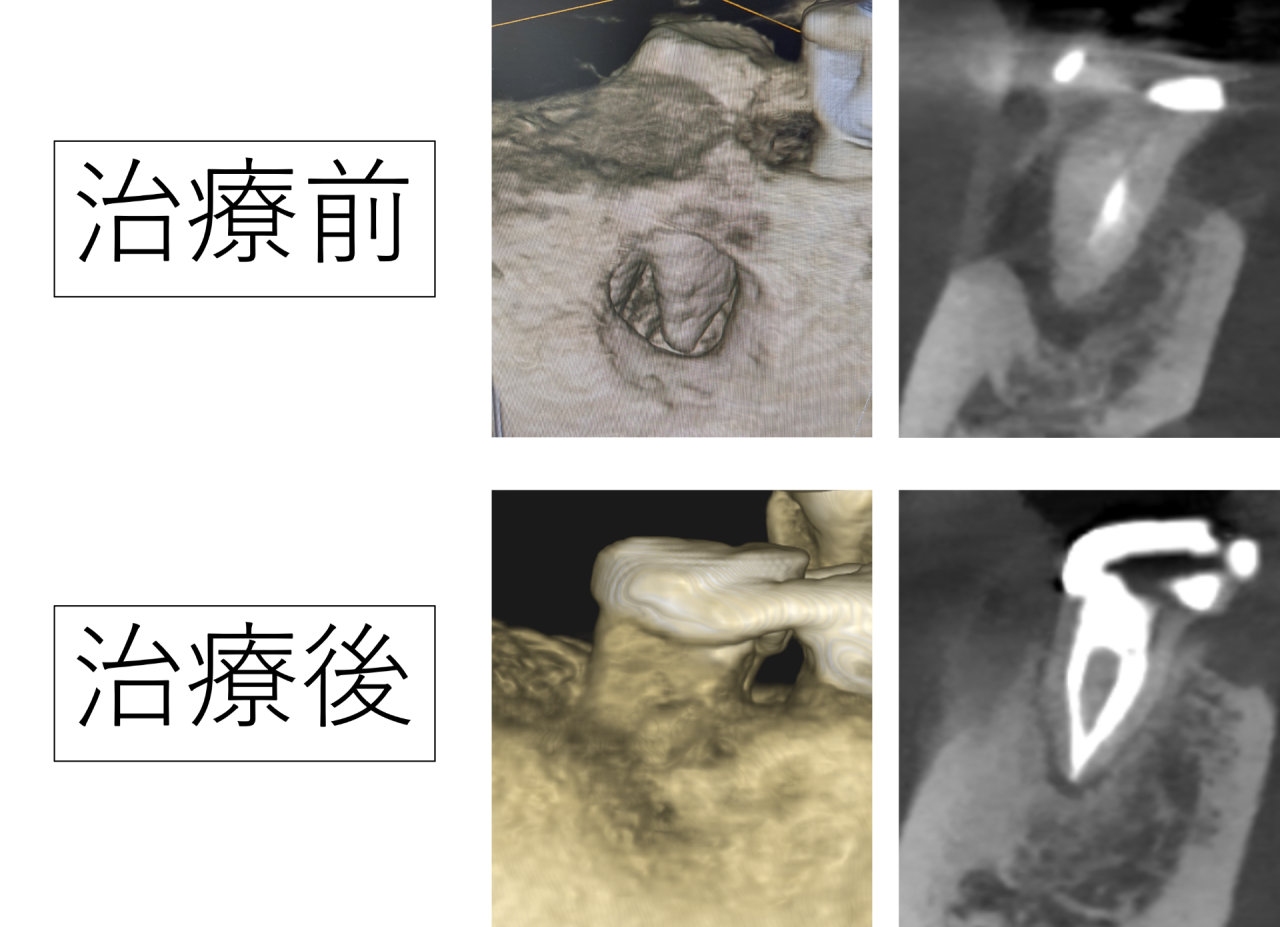

今回は神経の取り残しによって、穴が開くほど顎の骨が大きく溶けてしまった歯を精密な根管治療を行い、骨が再生した症例を紹介いたします。

患者様は、右下の一番奥の歯がかんだ時に痛みがあり歯ぐきにできものが出来ていて膿が出る、とのことでいらっしゃいました。検査をすると、内側の歯ぐきにできものが出来ていて、膿が出ていました。

レントゲンを詳しく確認しました。横からの断面図を見ていくと、以前の治療で神経を取って薬をつめているのですが、神経の取り残しがあり、薬が根の先まで十分に入っていません。取り残された神経が腐ってしまい、根の中で細菌が繁殖し、根の外に出てしまい顎の骨を溶かしてしまっています。

前からの断面図を見ると、黒い部分が骨が溶けているところですが、とても広範囲にわたり骨が溶けているのがわかります。

立体化した画像では、骨が溶けてしまい大きな穴が開いてしまっています。歯の根っこが丸見えの状態です。